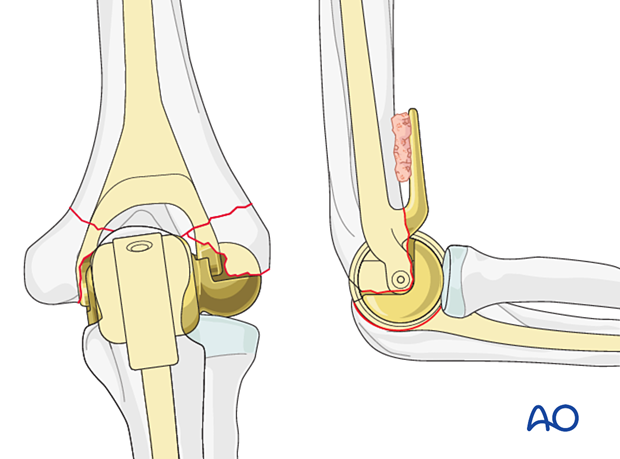

- Components: The procedure involves removing the damaged parts of the elbow joint, including the humeral (upper arm bone) and the ulnar (forearm bone) components, and replacing them with artificial components. The artificial joint generally consists of a metal prosthesis and a plastic liner that mimics the natural motion of the elbow joint.

- Approach: The surgeon makes an incision along the back of the elbow, carefully removes the damaged joint surfaces, and positions the prosthesis.